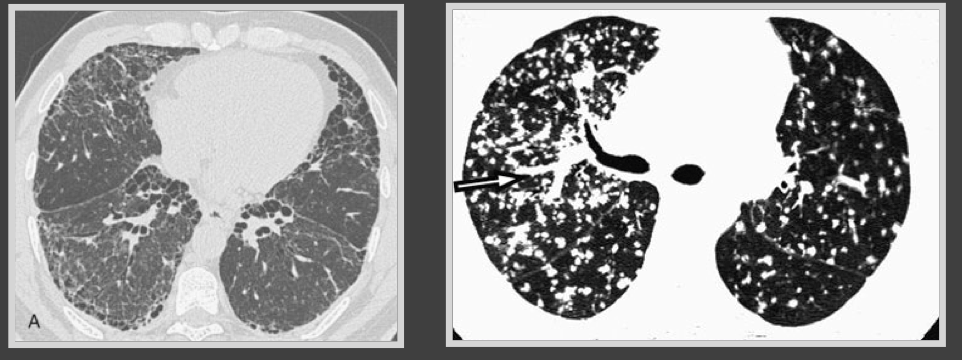

What stage of lung disease is this person in?

Reticular - ground glass appearance seen here. This patient is at the intermediate stage and will never improve to full lung function

What stage of ILD is seen here?

This is the earlier ground glass phase

What stage of ILD is this?

End-stage - honeycombing (you are screwed)